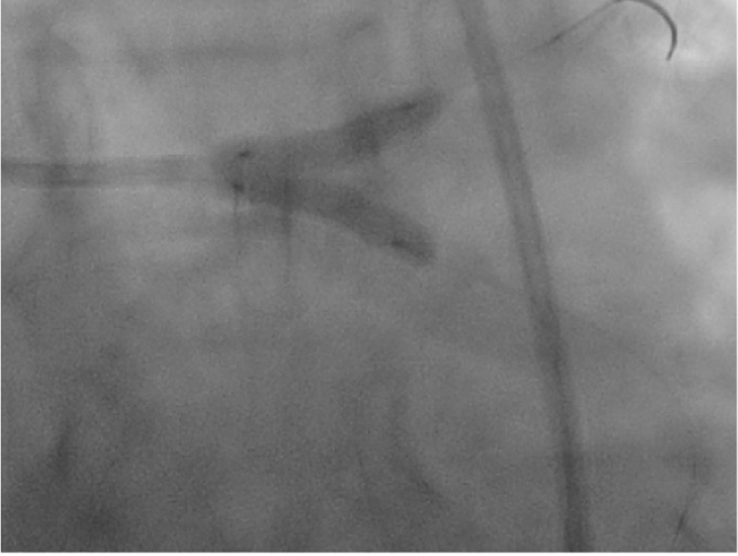

🫀Left anterior descending coronary artery occlusion after balloon aortic valvuloplasty Read at tinyurl.com/mrxznm2a #cardiology #interventionalcardiology #cardiologyfellow #cardiologia #echocardiography #cathlab #ECG #cardiovascular #electrocardiography #cardiac #ITcardiology

🫀Left anterior descending coronary artery occlusion after balloon aortic valvuloplasty

Read at tinyurl.com/mrxznm2a